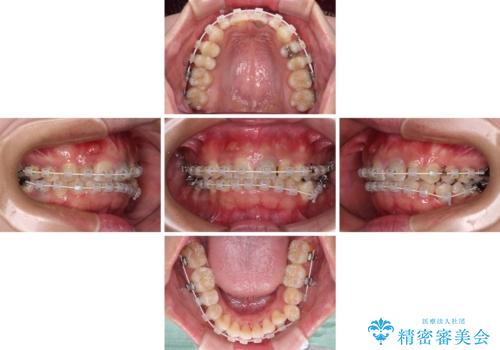

- 矯正装置

- 審美装置

- 治療期間

- 2年5ヶ月

矯正治療は、小臼歯1本分を歯列に納めないいけない状態であったため、表側のワイヤー装置にて行うこととしました。

下顎の小臼歯を移動しきるのに2年弱の期間を要することとなり、補綴治療も合わせて2年半ほどの治療期間となりました。